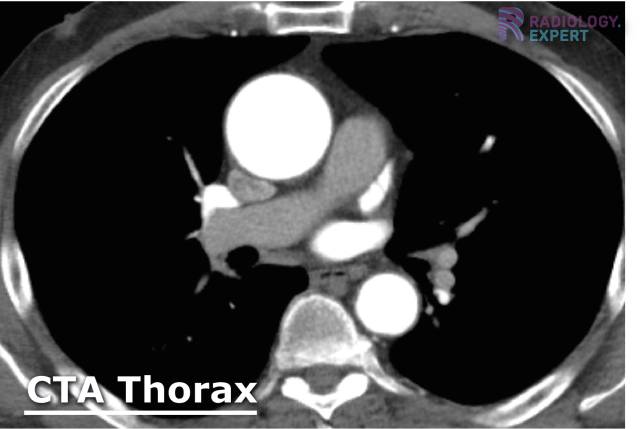

Of all the imaging techniques CT gives the most information on the lung parenchyma. It can be used following an X-ray or inconclusive US. Through use of intravenous contrast, we can further image vascular structures and assess blood flow or perfusion (fig 8).

Figure 8. CT angiography (CTA) of the thorax. Transverse section of an aneurysm of the ascending aorta. Note the dense (white) contrast agent, primarily found in the aorta and less so in the pulmonary artery; in this way the aorta can be properly assessed.